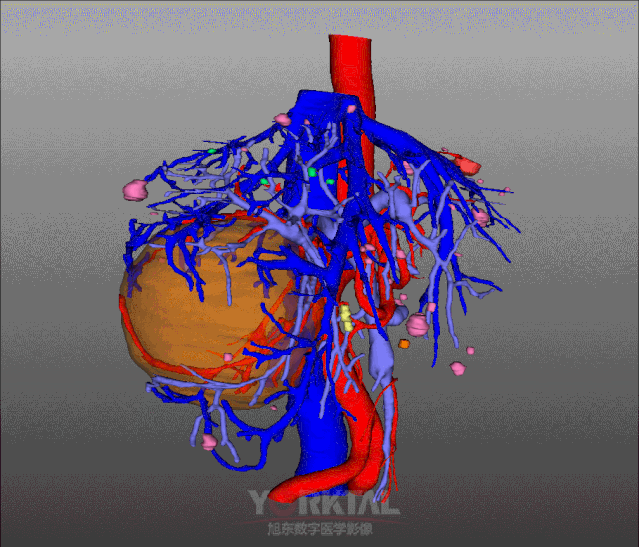

三维可视化术前影像评估

三维可视化全景影像图

占位与动脉血管解剖关系

占位与门静血管解剖关系

占位与肝静脉解剖关系

3D可视化入路规划